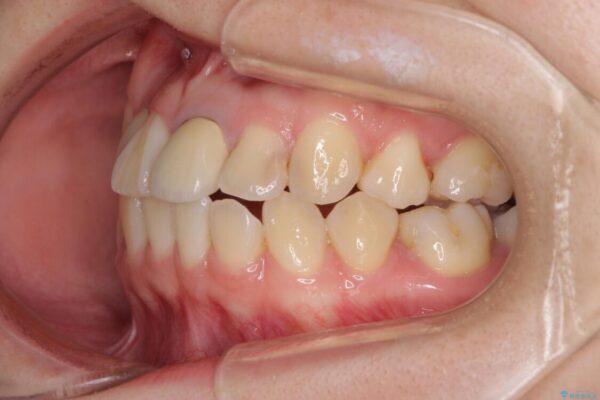

治療前

• 虫歯治療ついでに歯並びの後戻りを改善 インビザラインによる矯正治療 治療前画像

奥歯が痛いとのことで来院された患者様です。

治療計画

上顎親知らず周辺の炎症と、神経組織の失活した歯の炎症による痛みが認められたため、親知らずの抜歯と根管治療を行いました。

根管治療を行った歯はクラウンによる補綴治療が必要となりますが、高校生の頃に行った矯正治療の後戻りも気になるとのことで、補綴治療を行う前に矯正治療を行うこととしました。

後戻りは軽度であり、インビザラインにて歯列を整え、その後にオールセラミッククラウンにて補綴治療を行うこととしました。